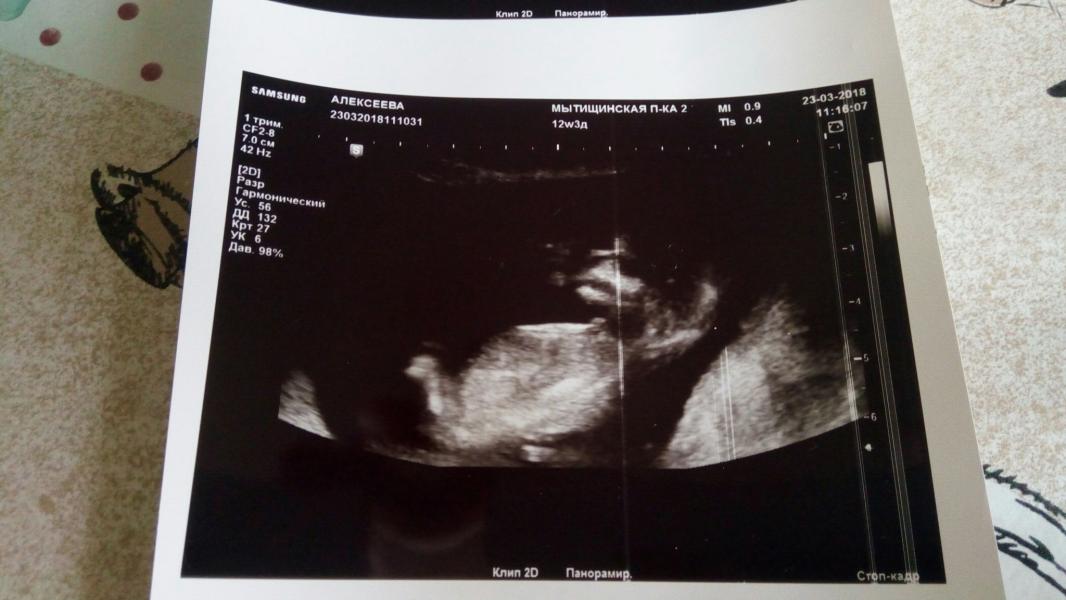

Была на первом скрининге и увы не чего не сказали(, тока фото на память дали) есть ли у нас в программе уже кто умеет определять по бугорку! интересно мнение). Я вот думаю можно на это пологаться если плод лежит не так как на фото в интернете по определению.) Сомневаюсь делать выводы, но очень хочется понять кто живёт внутри )

@dasha.sharina у них на этом сроке и у девочек и у мальчиков бугорок и он превращается либо в писюн или половые органы просто врачи могут померить угол этого бугорка, но им не до этого каждой мерить времени не хватит

@valentinka131 ну тока опытный врач узист может измерить угол этого бугорка и сказать, но им лень мерить (